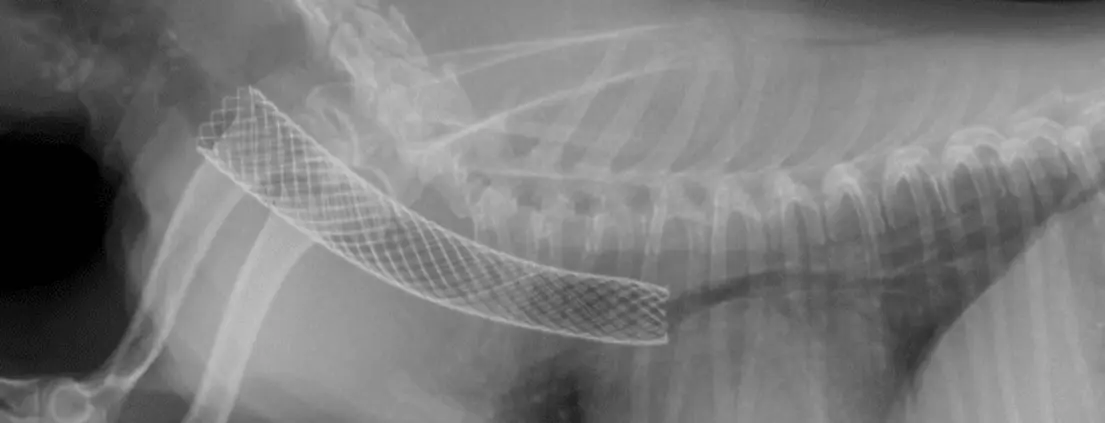

Tracheal Stents